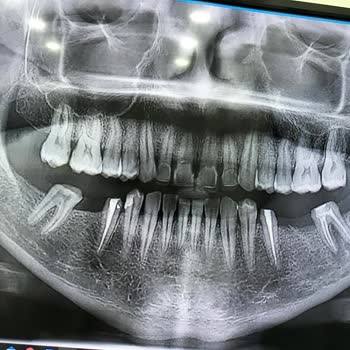

17.02.2025 tarihinde Kaynarca Alpi Diş Hastanesinin aciline gittim. Mevcutta kanal bulunan dişimin ağrıması ve yüzümün şişmesi dolayısıyla gittim. Daha önce başka bir hastaneye gözüküp dişin çekimine karar vermiştim fakat acil doktoru yaşımın küçük olduğunu (24) diş çekimine gerek olmadığını kanal t...